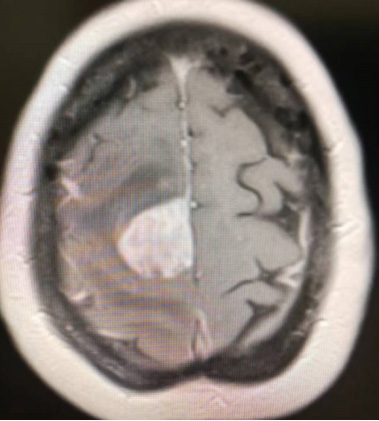

Case 3: A 65 year old male patient with cavernous hemangioma of the cavernous sinus, Figure A-B

Figure A: Localization of Gamma Knife Therapy from 2020 to 06 to 10

Figure B: 2021-06: After six months of gamma knife treatment, the lesion showed significant reduction